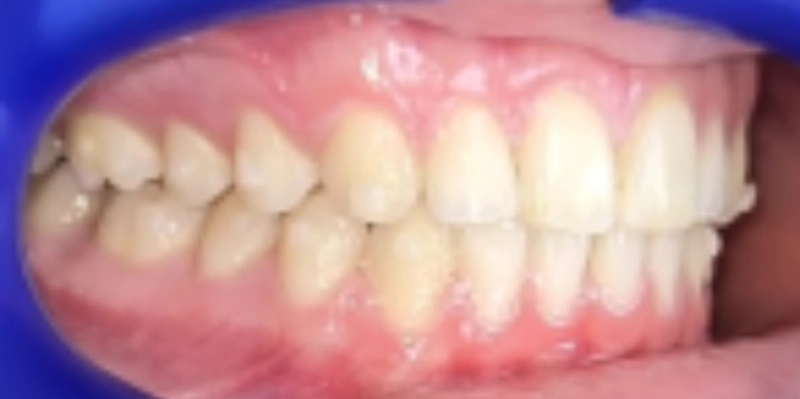

תמונות לפני ואחרי טיפול

לפני

ק.ר., בן 12, הגיע למרפאה עם מקרה אורתודונטי מורכב, שכלל שילוב של בעיה סגרית, צפיפות דנטלית ואתגר אסתטי משמעותי באזור הקדמי. בבדיקה נמצא סגר עובר אופקי מוגדל, סגר אסימטרי עם יחסי קלס 2 בצד ימין באזור הטוחנות, יחס טוחנות תקין בצד שמאל, אך יחסי קלס 2 באזור הניבים בשני הצדדים. בנוסף נצפתה צפיפות באזור החותכות העליונות, עם חפיפה בין שיניים 11 ו 21, וכן צפיפות גם בקשת התחתונה.